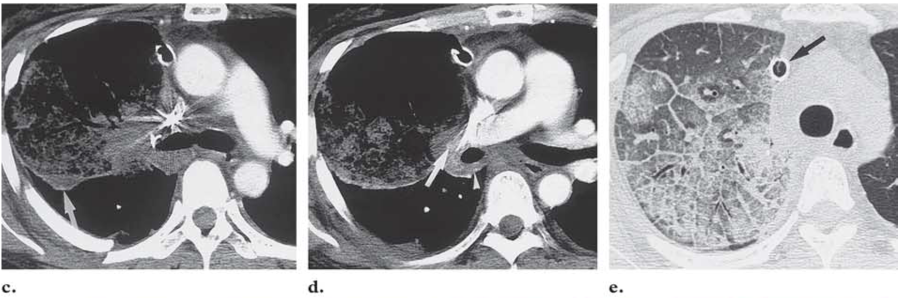

REF: Radiographic and CT Findings in Complications Following Pulmonary Resection

lung torsion engorgement renaud renato poumon lungs parenchym lobe lobaire rotation torsion incarcération